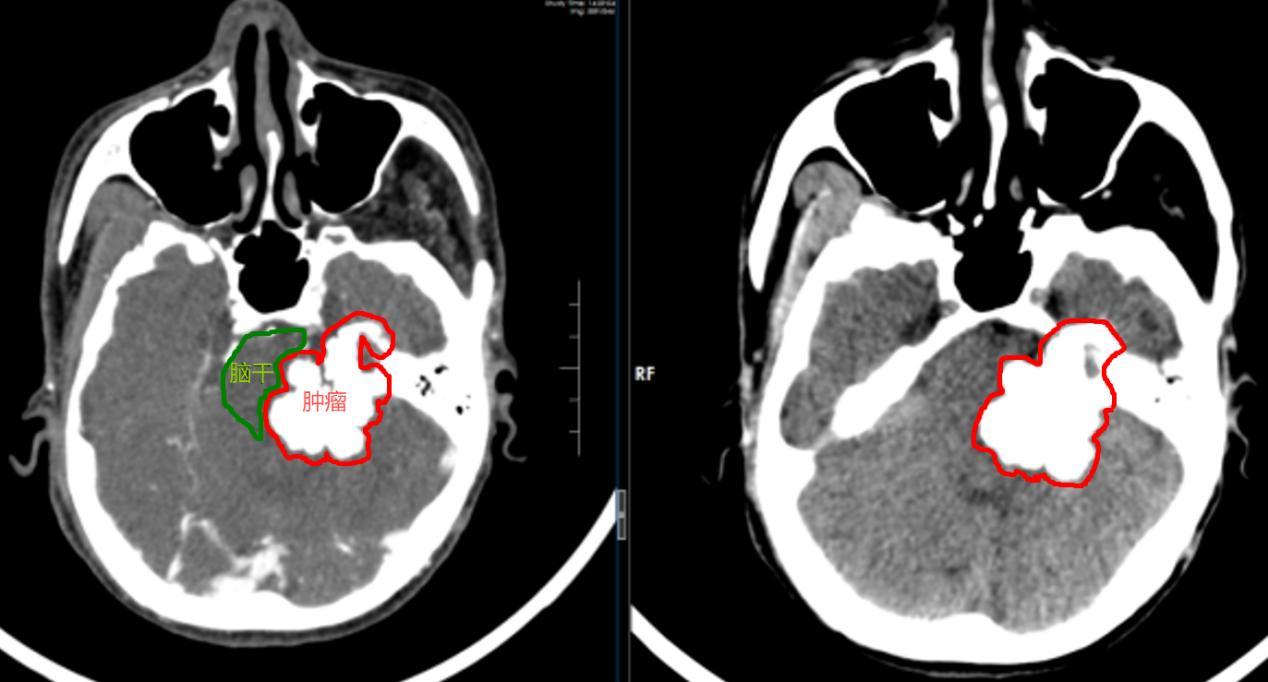

该院神经外五科学科带头人鲁明接诊后,结合患者的既往病史和影像检查结果,明确诊断为左侧桥小脑角占位性病变,肿瘤挤压脑干,导致患者出现左侧肢体无力、左脸偏瘫、嘴角漏食等症状。

“脑干作为人体的‘生命中枢’,掌控着呼吸、心跳等基本生命体征。”鲁明建议立即手术切除肿瘤,一旦受压加重,不仅会导致肢体瘫痪,更可能引发脑疝,危及生命。

手术过程中,鲁明发现,患者颅内肿瘤坚硬如石头,与周围神经、血管及脑干组织粘连紧密,再加上患者有过脑肿瘤手术史,颅内情况更为复杂,进一步增加了手术难度。

经过十余小时的奋战,手术团队终于成功将一个34mm×49mm×34mm的“石头状”肿瘤切除,脑干及周围神经、血管功能得到有效保护。术后,黄伯恢复情况良好,虽说话声音仍较轻微,但生命体征平稳,正在逐步康复中。